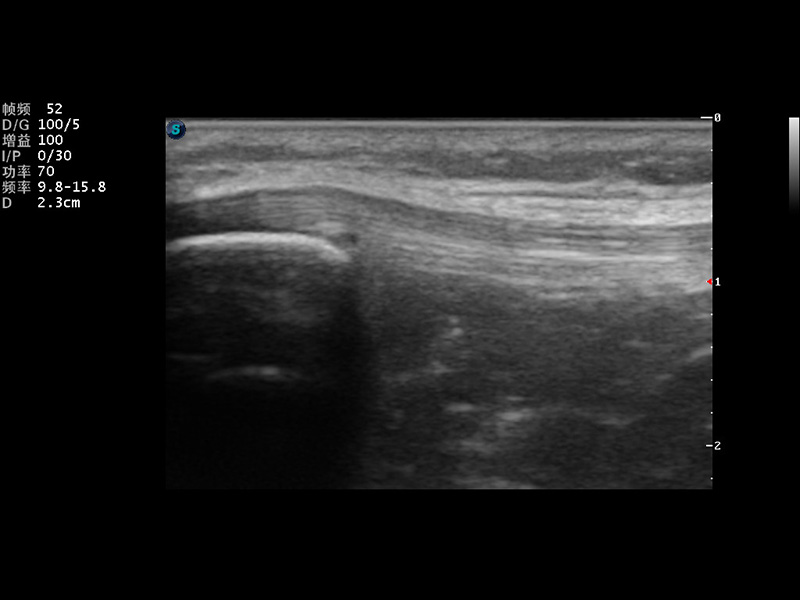

S9便携式彩色多普勒超声诊断仪是1xBET研发的高端便携彩超设备,外观设计新颖、产品性能卓越。S9在便携超声领域采用了突破传统的触摸屏交互设计,并以先进的软件硬件技术和设计理念,为您带来清晰的图像质量、稳定的工作性能和便捷的操作体验。

成像技术